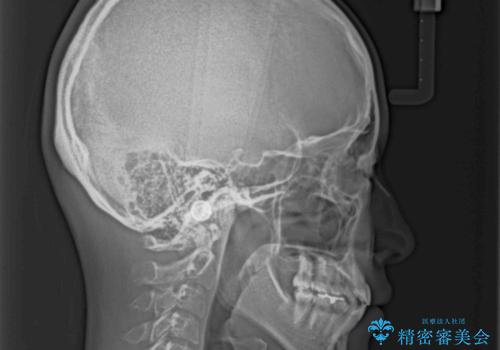

- 上下前歯が前方に飛び出しているとのことで来院された患者様です。

上下左右第一小臼歯4本を抜歯して、積極的に口元を引っ込めるよう、ワイヤー装置にて矯正治療を行うこととしました。

口元の突出感は著しく改善され、横顔の印象が大きく変化しました。